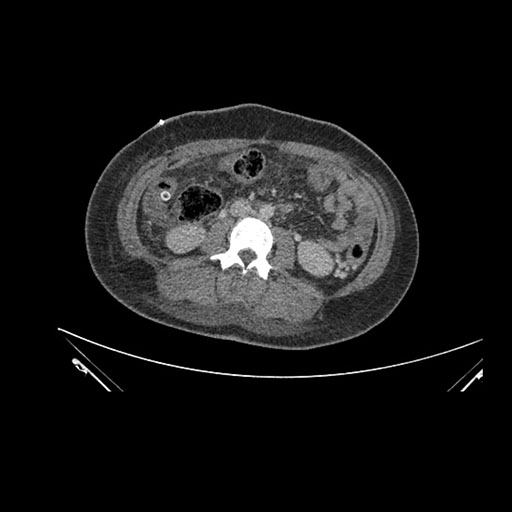

Axial Arterial

Axial Venous

Imaging analysis

Based on initial findings, which issue(s) would you be most concerned about?